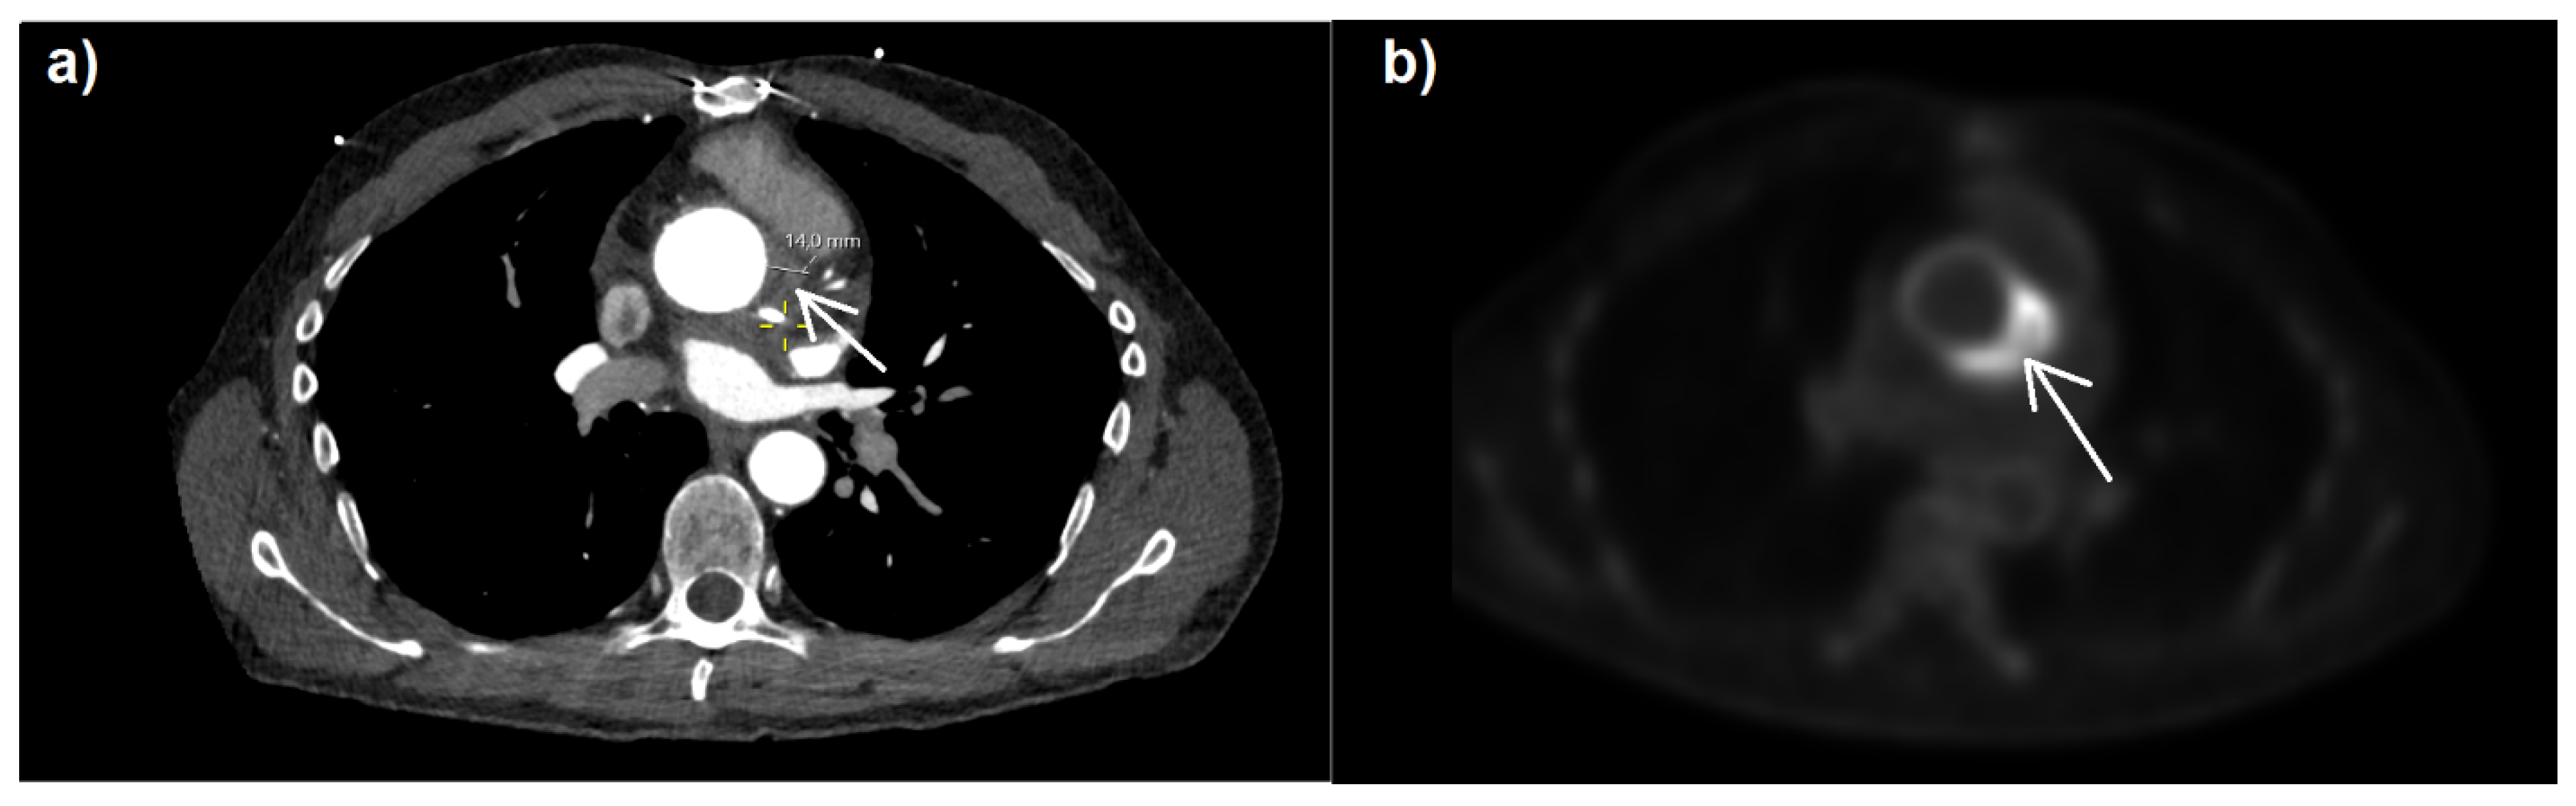

The patient had complained of muscle fatigue and ten kilogram weight loss over the previous six months. There was no elevation of body temperature. The laboratory evaluation demonstrated mildly elevated C-reactive protein levels (17 mg/L; <5 mg/L), with normal levels of procalcitonin (0.02 ng/mL; <0.5 ng/mL) and leukocytes (5.9/nL; [3.5–10]/nL), as well as hemoglobin concentration (12.3 g/dL; [5.5–13, 13–17] g/dL). No petechiae, Janeway lesions, Osler’s nodes, splinter hemorrhages, or Roth spots were observed. A transesophageal echocardiogram revealed no vegetations on the aortic valve. A transthoracic echocardiogram revealed a good left ventricular function (LVEF 55%), a mild aortic regurgitation (Vmax 1.9 m/s, Pmax/mean 15/7 mmHg, AVA 2.3 cm2, VTI 15.4 cm), and no regional wall motion abnormalities. The patient had dyspnea with NYHA classification of II, good left ventricular function (LVEF 55%), and no signs of heart failure due to paravalvular leakage of the prosthetic valve. Further inspection through [18F]-fluorodeoxyglucose positron emission tomography–computed tomography (18F-FDG PET-CT) (Figure 1) revealed highly elevated glucose metabolism around the aortic valve ring and hematoma, indicating a florid inflammatory process.

Figure 1. CT (a) and 18F-FDG PET-CT (b) images with attenuated correction in cardiac CT/PET (b) and increased FDG uptake (white arrow) around the aortic valve annulus. Department of Nuclear Medicine, University Medical Center Mainz, Germany.